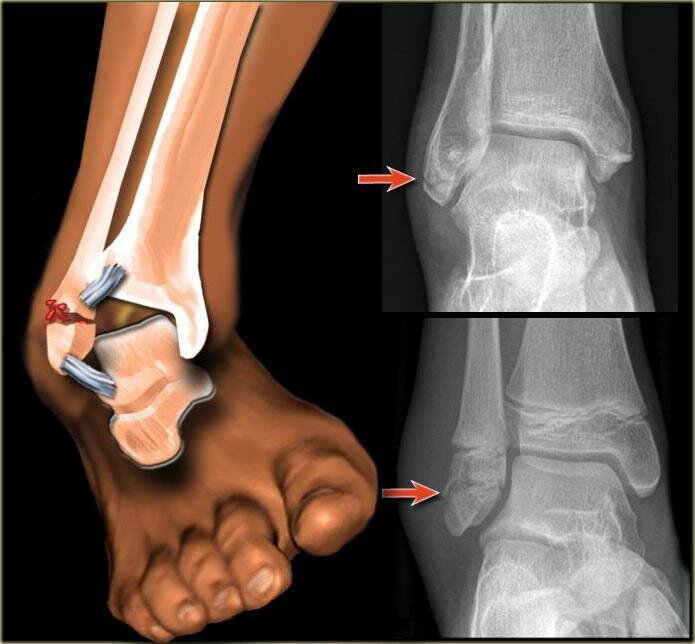

Перелом лодыжки чаще всего возникает при сильном ударе, падении, дорожно-транспортном происшествии, а так же оступившись, поскользнувшись и подвернув ногу. Часто травму может спровоцировать ношение неудобных туфель на высоких каблуках. В практике в основном  можно встретить закрытый перелом лодыжки. Для данного вида характерно отсутствие открытой раны. Обычно после перелома лодыжки опухает голеностоп, больной не может идти или даже стоять на ноге, а любые попытки движения вызывают сильнейшую боль. Переломы бывают со смещением и без смещения. При переломе без смещения болевой синдром и другие клинические признаки могут проявляться слабо.  Однако, при отсутствии своевременного лечения, кость будет срастаться неправильно, и у пациента могут проявиться такие неблагоприятные последствия, как привычный вывих голеностопа, формирование ложного сустава, хронические болезненные ощущения, нарушения двигательной активности, вторичный артроз.  Варианты лечения перелома лодыжки: Выполненная качестве

Переломы бывают со смещением и без смещения. При переломе без смещения болевой синдром и другие клинические признаки могут проявляться слабо.